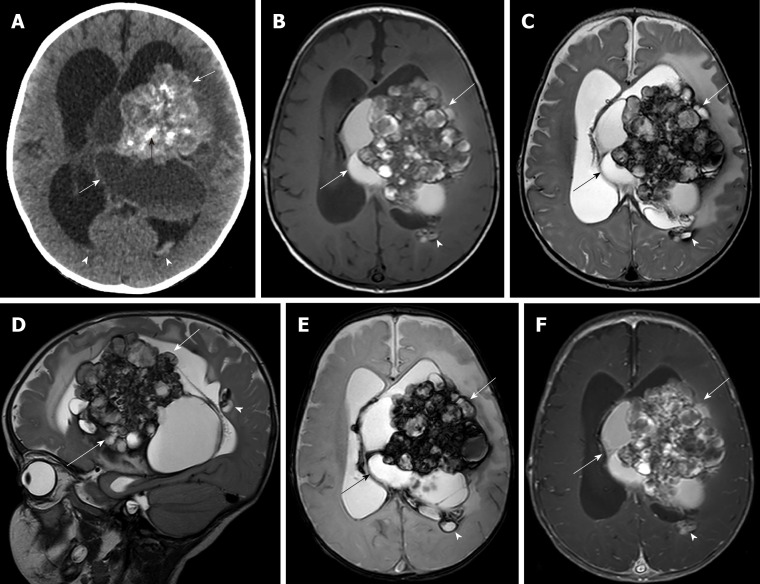

影像检查:脑计算机断层扫描(CT)显示一个混合的囊实性脑室肿瘤,伴有多个内部钙化,涉及侧脑室和三脑室的体部和三角区,伴有严重脑积水(图1A).脑部磁共振成像(MRI)显示一个大的混合微小不均匀增强的囊实性脑室内肿块,伴有内部钙化和病灶周围脑水肿,主要位于左侧侧脑室的左三角区和体部,导致中度脑积水、低钙血症和左侧降小脑幕疝。在左右侧脑室后部可见另外两个小的室管膜下结节。发现相关的脑室内出血和蛛网膜下腔出血(图1B)。根据核磁共振检查结果,初步诊断为脉络丛乳头状瘤。

图1,术前脑计算机断层扫描和磁共振成像。A:非对比计算机断层扫描显示左侧侧脑室体囊实性肿块(白色箭头),内部钙化(黑色箭头),脑室内出血(箭头),导致脑积水;B:轴位T1加权像;C:轴位T2加权像;D:矢状T2加权像;E:轴T2*加权像;注射钆后轴位T1加权像显示左侧三角区和左侧侧脑室体部的实性-囊性脑室内肿块(箭头),伴有内部钙化、病灶周围脑水肿和不同程度的出血;血泡外观。在左侧脑室后部的室管膜下区域可以看到另一个微小的增强结节(箭头)。